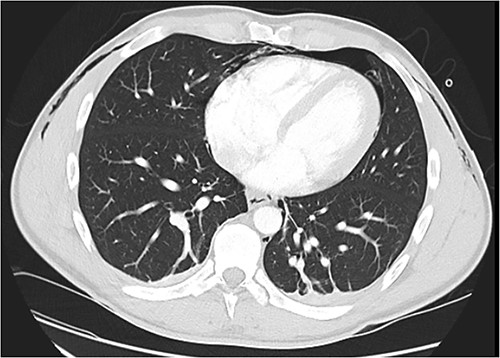

Following extubation, bilateral chest wall subcutaneous emphysema was noted extending to the neck. He also complained of central chest discomfort, without respiratory distress, oxygen desaturation or airway obstruction. Chest X-ray (CXR) revealed pneumomediastinum and surgical emphysema in the lateral chest walls bilaterally. Computed tomography (CT) of the chest, abdomen and pelvis demonstrated large volume subcutaneous emphysema bilaterally in the scrotum, abdominal and chest walls extending to the neck (see Figs 2–5). Gas was noted between the abdominal muscle layers, extraperitoneal and retroperitoneal spaces without pneumoperitoneum (see Figs 5–6). Moderate pneumomediastinum was prominent within the superior and antero-inferior mediastinum without evidence of tracheal or oesophageal injury and an associated small left pneumothorax was noted (see Figs 1–3).

CT chest axial, small left pneumothorax and chest wall subcutaneous emphysema.